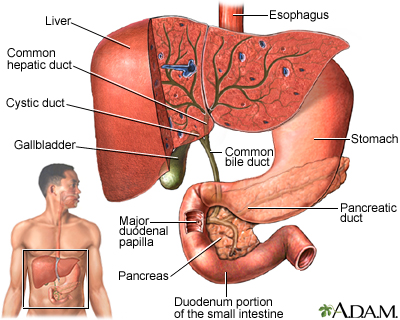

Choledocholithiasis means there is at least one gallstone in the common bile duct. The stone may be made up of bile pigments or calcium and cholesterol salts and are called common bile duct stones.

About 1 in 7 people with gallstones will develop stones in the common bile duct. This is the small tube that carries bile from the gallbladder to the intestine.

The goal of treatment is to relieve the blockage of the common bile duct.

- ERCP and a procedure called a sphincterotomy, which makes a surgical cut into the muscle in the common bile duct to allow stones to pass or be removed